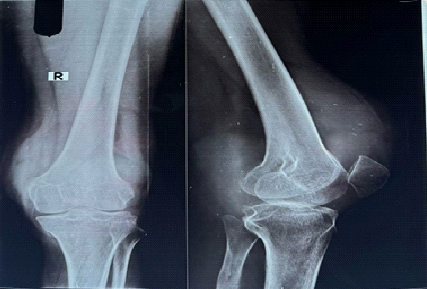

A 42-year-old male, employed as a bank clerk, presented to our orthopedic outpatient department with a chief complaint of gradually progressive pain and swelling in the posterior aspect of his left knee for the past 18 months. The pain was insidious in onset, initially mild and intermittent, but had progressively worsened in intensity over the past 6 months, becoming persistent and affecting daily activities. The patient reported that the pain increased during prolonged standing, walking, or ascending stairs, and was partially relieved by rest and over-the-counter nonsteroidal anti-inflammatory drugs (NSAIDs). He also noted a feeling of fullness and a palpable lump in the back of his knee for the past 4 months, which he described as firm and slowly enlarging. There was no history of trauma, recent infection, or previous knee surgery. His medical history was unremarkable, with no known metabolic, rheumatologic, or malignant conditions. He denied any constitutional symptoms such as fever, weight loss, or night sweats. On clinical examination, the patient was of average build and appeared in no acute distress. Inspection of the left knee revealed no gross deformity but a subtle fullness in the popliteal fossa, more prominent when the knee was extended. On palpation, a firm, well-defined, non-tender mass approximately 5 cm × 3 cm was felt in the posterior-medial aspect of the knee, deep to the soft tissues. No warmth or erythema was overlying the swelling. The range of motion of the knee was from 0° extension to 95° flexion, with terminal flexion eliciting pain and a sense of tightness in the posterior aspect. Ligamentous stability tests (anterior drawer, posterior drawer, varus-valgus stress) were normal. Patellar tracking was intact, and there was no crepitus on movement. Neurovascular examination showed intact distal pulses (dorsalis pedis and posterior tibial arteries palpable) and normal sensory and motor function in the lower limb, indicating no neurovascular compromise. Initial radiological evaluation with plain anteroposterior and lateral X-rays of the left knee (Fig. 1) demonstrated multiple, small, well-defined calcified loose bodies located predominantly in the posterior aspect of the joint, without significant joint space narrowing or evidence of degenerative changes. The bony contours of the femur and tibia appeared normal, and no fractures or osteophytes were noted. These findings raised the suspicion of synovial chondromatosis. Given the location of the lesion and the possibility of extra-articular extension, MRI was performed for better characterization (Fig. 2, 3).

Figure 1: Pre-operative X-ray (anteroposterior and lateral) showing multiple calcified intra-articular loose bodies.